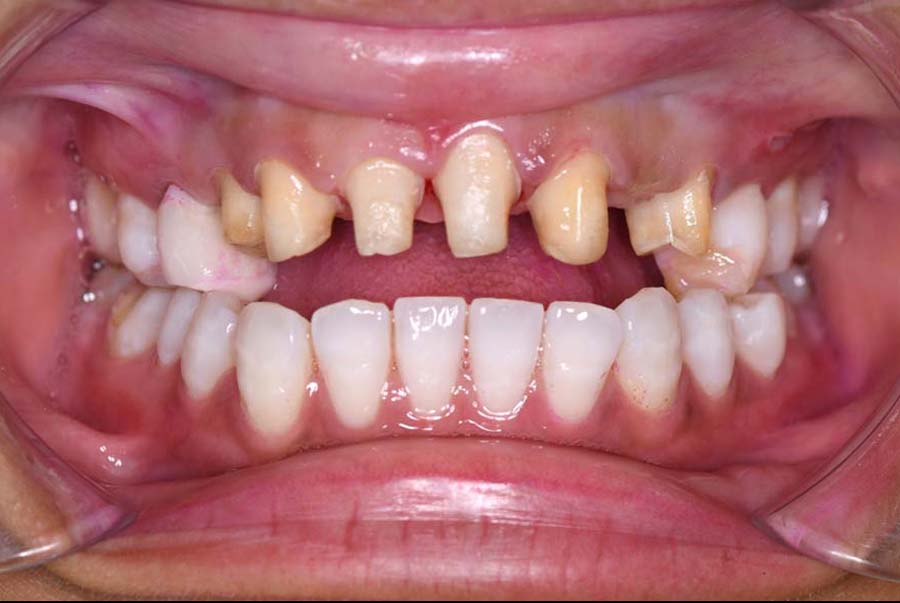

噛み合わせ治療の症例24

スプリント使用後、

補綴治療をした症例

| 主訴 | 噛み合わせが悪い |

| 期間 | 約2年2ヶ月 |

| 治療内容 | ①スプリントを装着 ②副子を装着 ③2024年4月 口腔内反映開始 ④副子を入れた状態の所まで咬合を挙上 (バイトアップ) ⑤2024年5月 上顎前歯部8本へ仮歯(TEK) を装着 |